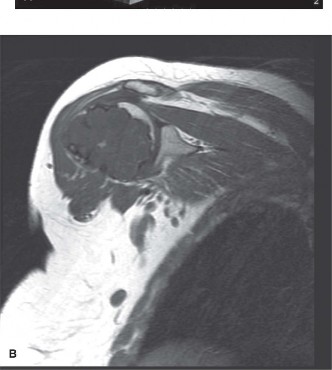

Magnetic Resonance Imaging Characterization

MRI of the left femur with and without intravenous gadolinium contrast was obtained to evaluate the marrow extent, skip lesions, and potential soft tissue extension. The T1-weighted coronal images demonstrated a well-demarcated area of low to intermediate signal intensity replacing the normal high-signal fatty marrow of the proximal femur. The lesion extended from the intertrochanteric line distally for approximately 12 centimeters.

Axial T2-weighted and STIR (Short Tau Inversion Recovery) sequences revealed the classic hyperintense, lobulated appearance of hyaline cartilage. The high water content of the cartilaginous matrix results in a bright signal on fluid-sensitive sequences. Low-signal septations were visualized between the cartilaginous lobules. Importantly, the MRI confirmed the absence of a soft tissue mass and verified that the cortical boundary, while severely thinned, remained intact.